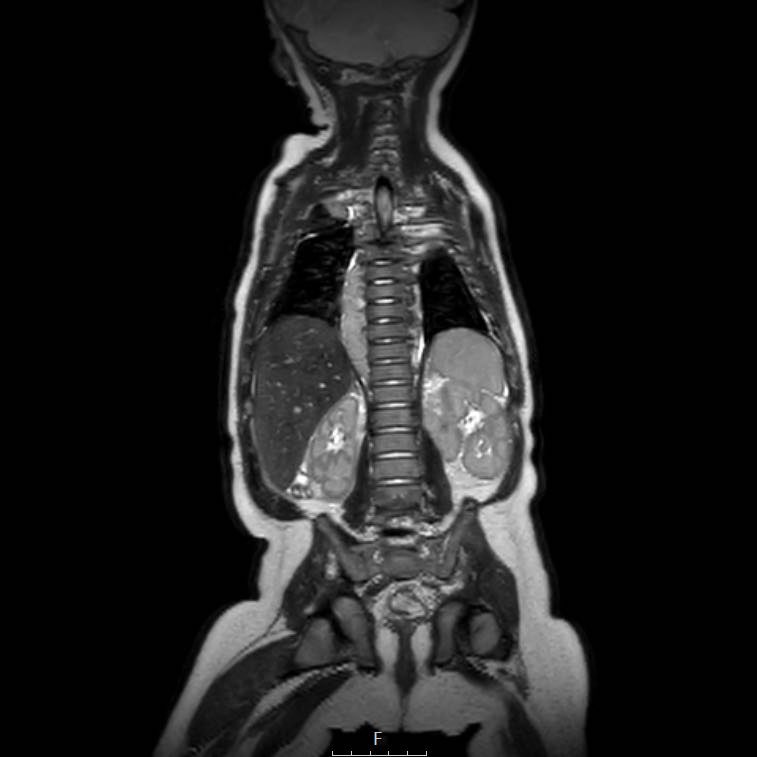

Cuộn qua chuỗi ảnh T2 theo mặt phẳng coronal.

Nghiên cứu các hình ảnh và sau đó tiếp tục đọc.

The findings are:

- Mass with encasement of the aorta and splanchnic vessels.

- Lan rộng dọc theo cột sống ngực nhưng không xâm lấn vào ống sống.

- Small liver metastases.

- Left supraclavicular mass.